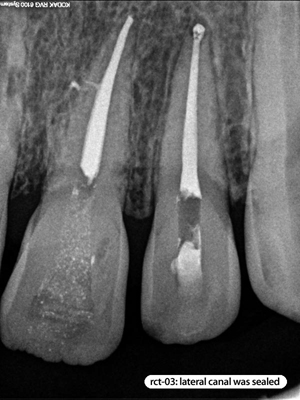

Root Canal Cases